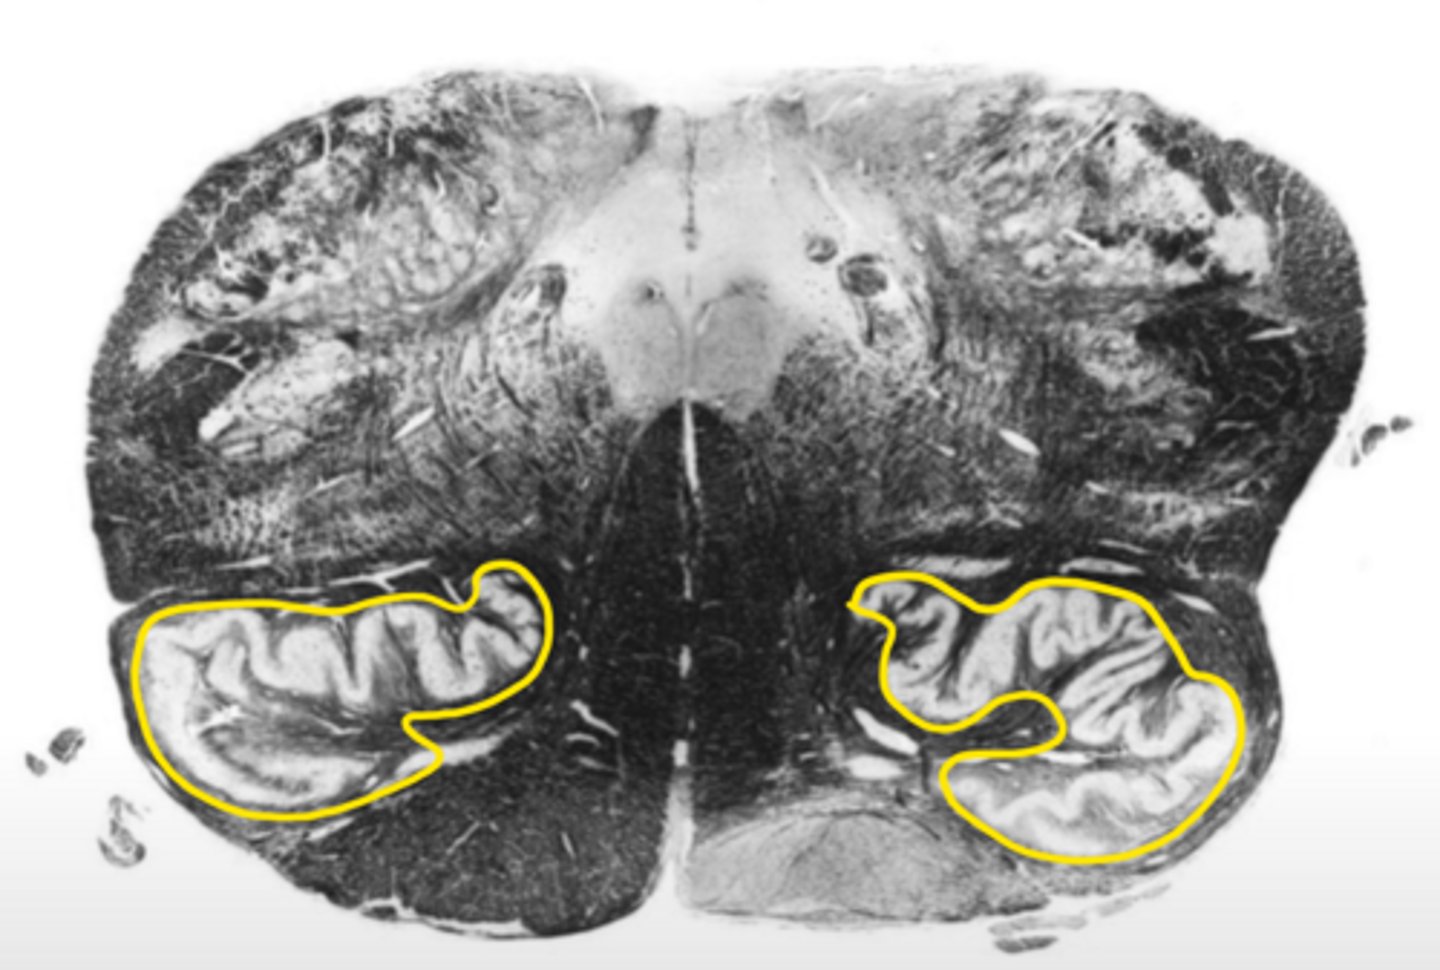

open medulla

ID the area

ID the brainstem level